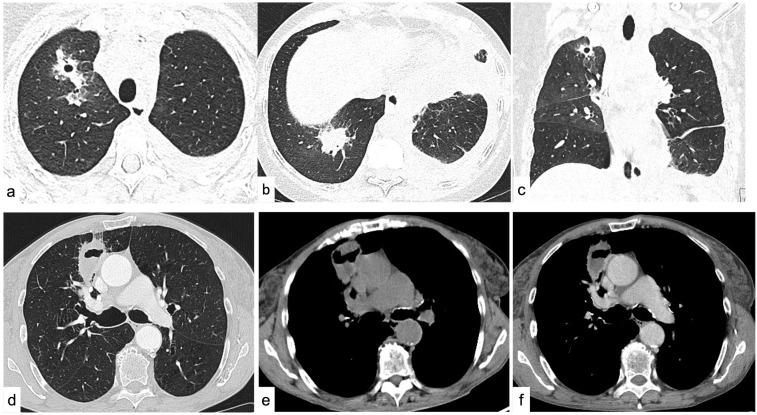

This review has the purpose of illustrating schematically and comprehensively the key concepts for the beginner who approaches chest radiology for the first time. The approach to thoracic imaging may be challenging for the beginner due to the wide spectrum of diseases, their overlap, and the complexity of radiological findings. The first step consists of the proper assessment of the basic imaging findings. This review is divided into three main districts (mediastinum, pleura, focal and diffuse diseases of the lung parenchyma): the main findings will be discussed in a clinical scenario. Radiological tips and tricks, and relative clinical background, will be provided to orient the beginner toward the differential diagnoses of the main thoracic diseases.